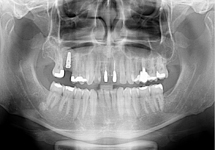

Nejčastější oblastí pro doplnění kosti je čeleni dutina horní čelisti.

Tento výkon se nazývá sinus lift - aplikace kostního granulátu do čelistní dutiny

Při ztrátě molárů a premolárů v horní čelisti a jejich náhradě implantáty se často setkáváme s nedostatečnou vertikální nabídkou kosti pod čelistní dutinou, často doprovázenou i nedostatečnou horizontální nabídkou a sníženou kvalitou kosti

(v oblasti 2. premoláru v 50%, v oblasti moláru až v 80% případů nedostatečná kostní nabídka)

Od roku 1985 je tento problém řešen augmentační operací nazývanou sinus lift.

Vhojení implantátů se při této operaci prodlužuje na 6-12 měsíců.